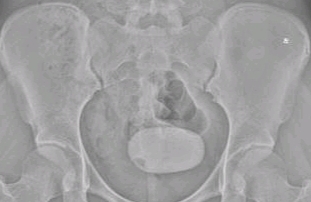

來自永州市新田縣冷水井鄉(xiāng)的一名16歲年輕女士尹女士,排尿時偶有不暢,需要用力按壓小肚子才能排出,但癥狀不嚴重,于是一直未放在心上。一個月前患者出現(xiàn)排尿困難、尿頻、尿急、尿痛,嚴重影響了日常生活,于是來到我院就診,行泌尿系彩超及腹部立位平片被診斷為膀胱巨大結石。

手術主要由我科曾向陽博士、徐旭紅副主任醫(yī)師完成,在醫(yī)師細心操作下,一個似鴨蛋般大的“巨大”結石呈現(xiàn)在醫(yī)生面前,該膀胱結石呈圓形,直徑約為8厘米。